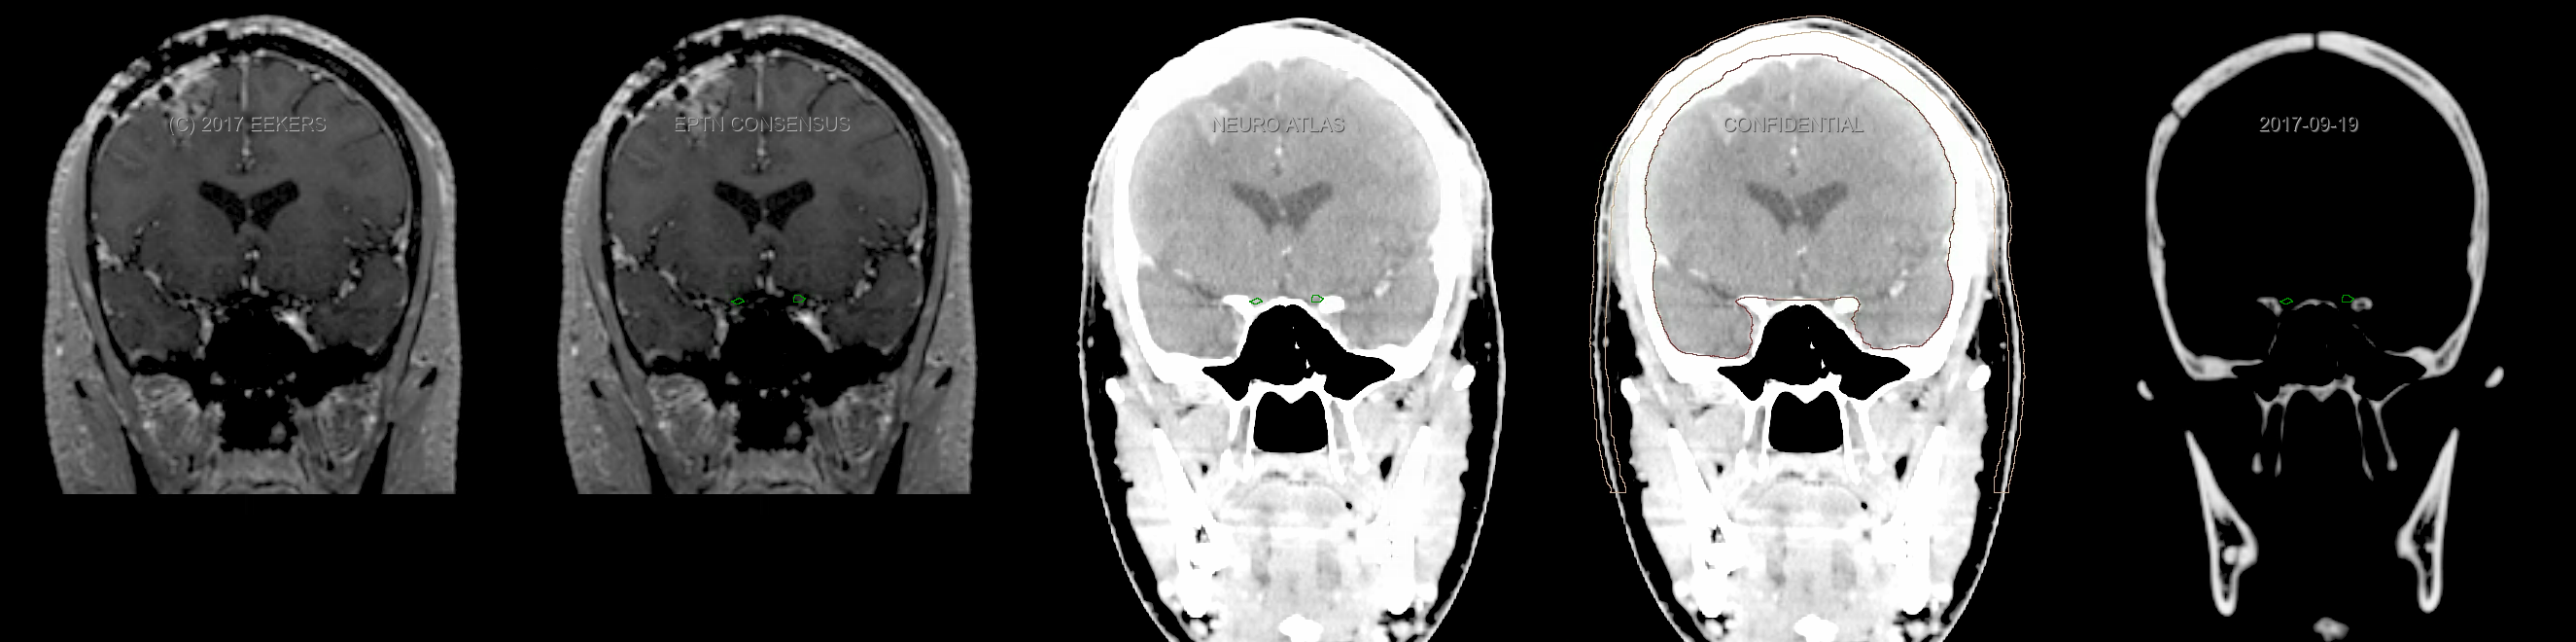

Eekers et al. have published an international neurological atlas for contouring of organs at risk in consensus with the European Particle Therapy Network (EPTN). The purpose of this consensus atlas is to decrease inter- and intra-observer variability in delineating OARs relevant for neuro-oncology. We propose this atlas is used in photon and particle therapy in order to derive consistent dosimetric data. When required this atlas will be updated according to new insights.

Included are all OARs known to be relevant for radiation-induced toxicity in neuro-oncology: brain, brainstem, cochlea, vestibulum & semicircular canals, cornea, lens, retina, lacrimal gland, optic nerve, chiasm, pituitary, hippocampus and skin. A new OAR relevant for neuro-cognition, the posterior cerebellum is also included.

Three-dimensional delineation of the fifteen consensus OARs for neuro-oncology are shown on CT and 3 Tesla (3T) MR images (slice thickness 1 mm with intravenous contrast agent). All are presented in transversal, sagittal and coronal view.

From left to right: MR without structures, MR with structures, CT (WW/WL 120/40) with structures, CT (WW/WL 120/40) with Brain and Brainstem Surface, CT (WW/WL 1500/120)with structures